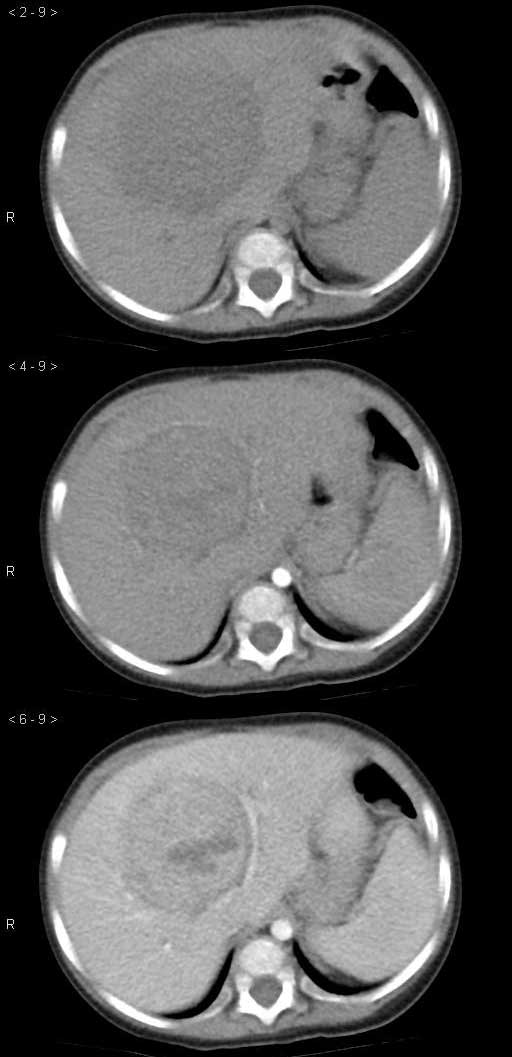

男孩,7个月,因呕吐1个月就诊,超声提示肝脏占位。

实验室检查:AFP明显升高。

诊断:肝母细胞瘤

肝内单发占位,50%病例有钙化灶,病变边界清楚,增强扫描不均匀强化,内部可见无强化坏死区。

肝右叶可见巨大低密度占位,边缘欠光整,动脉期,肿块周边结节强化,内见分隔及条片状低密度影,门脉期,分隔进一步强化,肿块密度低于肝实质,考虑肝母细胞瘤可能性大。